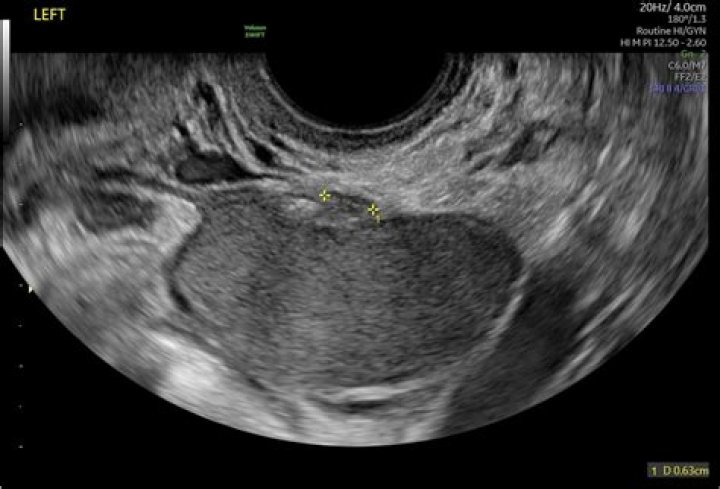

We have shown that identifying the subserosal hypoechoic rim and endomyometrial junction indistinctness on ultrasound scans can reliably help to distingui...